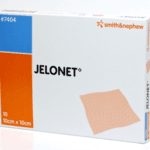

Apply Jelonet

TO provide a non-adherent moist dressing to preserve tissue viability